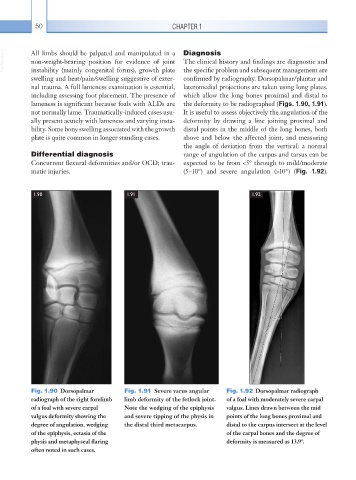

Fig. 1.90 Dorsopalmar Fig. 1.91 Severe varus angular Fig. 1.92 Dorsopalmar radiograph

radiograph of the right forelimb limb deformity of the fetlock joint. of a foal with moderately severe carpal

of a foal with severe carpal Note the wedging of the epiphysis valgus. Lines drawn between the mid

valgus deformity showing the and severe tipping of the physis in points of the long bones proximal and

degree of angulation, wedging the distal third metacarpus. distal to the carpus intersect at the level

of the epiphysis, ectasia of the of the carpal bones and the degree of

physis and metaphyseal flaring deformity is measured as 13.9°.

often noted in such cases.

lameness is significant because foals with ALDs are the deformity to be radiographed (Figs. 1.90, 1.91).

not normally lame. Traumatically-induced cases usu- It is useful to assess objectively the angulation of the

ally present acutely with lameness and varying insta- deformity by drawing a line joining proximal and

bility. Some bony swelling associated with the growth distal points in the middle of the long bones, both

plate is quite common in longer standing cases. above and below the affected joint, and measuring

the angle of deviation from the vertical: a normal

Differential diagnosis range of angulation of the carpus and tarsus can be

Concurrent flexural deformities and/or OCD; trau- expected to be from <5° through to mild/ moderate

matic injuries. (5–10°) and severe angulation (>10°) (Fig. 1.92).